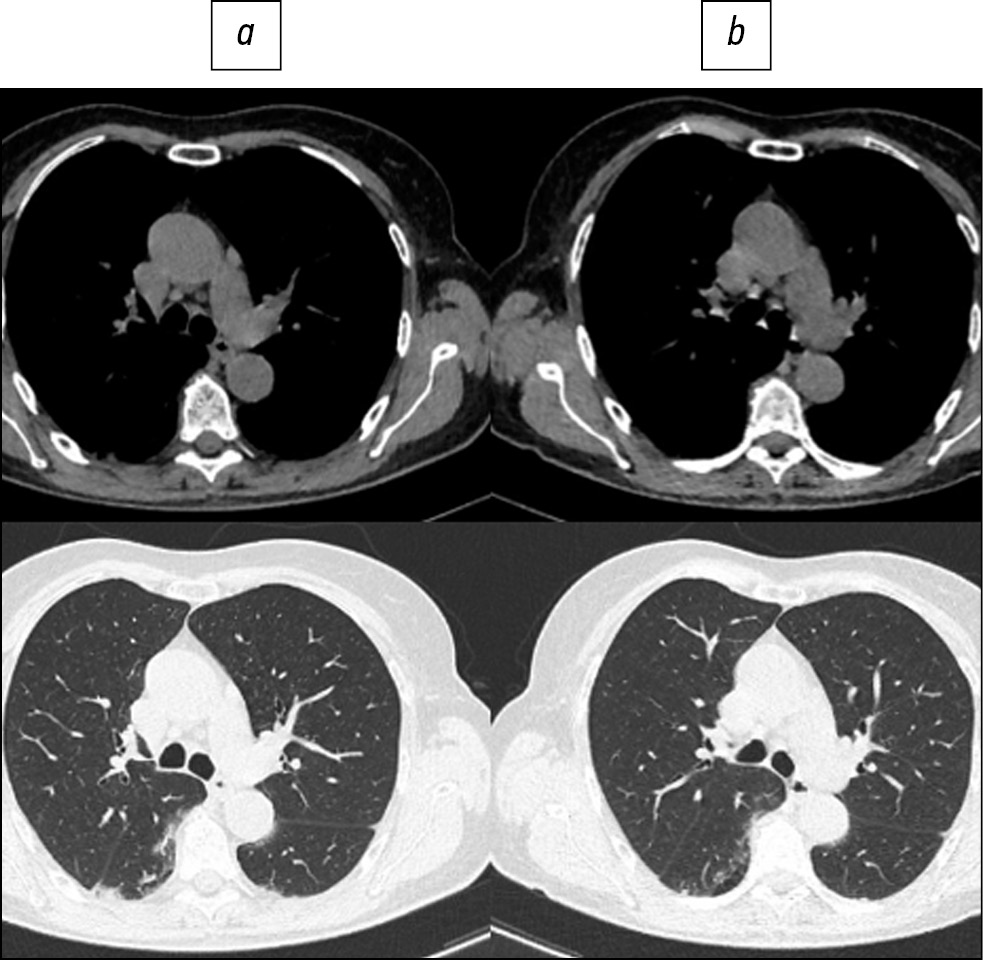

Fig. 5. Patient, 40 years old: standard computed tomography at admission was performed with radiation exposure of 6.8 mSv (a), low-dose computed tomography - 2.0 mSv (b).

Fig. 6. Patient, 56 years old: standard computed tomography at admission was performed with a radiation load of 1.6 mSv (a), low-dose computed tomography - 0.87 mSv (b).

Here are illustrative examples of clinical cases (Figs. 1–6), demonstrating the similarity of diagnostic value of two aforementioned research methods. Columns on the left (a) show images of a standard CT scan performed upon admission of the patient to the hospital, and columns on the right (b) present LDCT over time. The top line of images indicates the pulmonary window mode, whereas the bottom line indicates the mediastinal window mode. For comparison, values of radiation exposure in each case are presented. Time intervals between standard CT and LDCT were 2–7 days; thus, the primary endpoint was reached in all patients enrolled in the study.